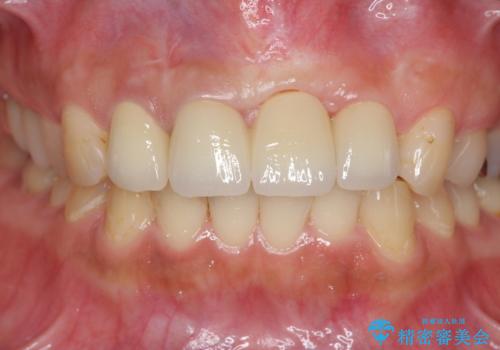

不良インプラントの除去・骨造成・歯肉移植・前歯審美セラミックブリッジ製作

不良インプラントを除去し最終的にブリッジによる補綴で審美性の改善を行うこと、その準備として骨の造成・歯肉の移植による歯の欠損部顎堤のボリュームを維持・増大を計画します。

より審美的な改善を強く求められたため、インプラントを除去し可及的に欠損部顎堤を増大したのちブリッジによる審美改善を行いました。